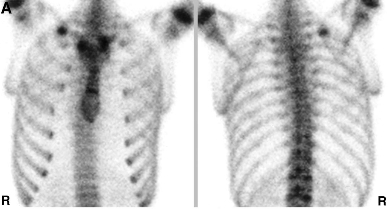

진단은 물론 X-ray 나 CT, bone scan 같은 영상검사로 하게 되지만

견갑골과 갈비뼈를 이어주는 Serratus anterior muscle 과 Rhomboid 안쪽 근육, Scapula 의 움직임 등으로 Rib cage 가 영향을 받을 수 있습니다. 행군을 많이하는 군인에게서 발목에 골절이 생기는 원리와 같습니다. 주로 나이가 든 분이나 여성에서는 앞쪽이나 근육 부착부위의 갈비뼈(4-9th)에 골절이 생기며, 남성에서 과하게 스윙 후 finish 를 하는 경우에는 좌측 견갑골과 갈비뼈의 충돌로 좌측 등쪽의 갈비뼈에 골절이 생깁니다. 프로 골퍼의 연습량이 늘었을때나, 주로 초보 골퍼에게서 후방 안쪽의 골절이 생깁니다.

외상의 골절과는 다르게 여러개의 뼈가 부러지는 형태가 아닌 단일뼈가 부러지는 형태의

피로골절 형태의 골절이 생기는 경우가 많습니다.